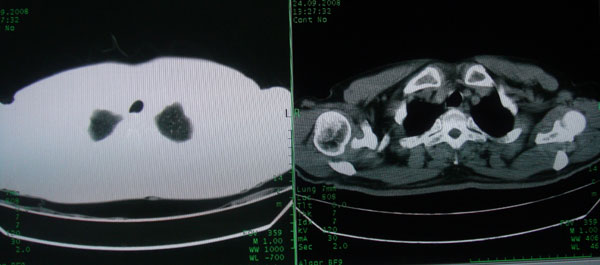

患者男性58岁因二周前起咳嗽,今天胸片示左上肺占位性病变行ct检查,无发热,无咯血痰.

左上肺感染性病变,结核伴空洞形成可能,左上肺膨胀不全

左肺上叶病灶,实变但见含气支气管、空洞但未见壁内结节及积液;

考虑:①感染性病变(包括特殊感染型肺tb)

②肿瘤性病变(考虑患者年龄比较大的关系/所以不排除)

初学者。。。左肺空洞性病变,并可见阻塞性肺不张改变,鉴于患者为老年男性,且临床症状仅有咳嗽,全身中毒症状不明显,所以我首先考虑为左肺癌性空洞并左侧肺门淋巴结转移伴左肺阻塞性肺不张。结核性空洞放于第二位考虑,可以进行相关实验室检查。希望能有病理结果,谢谢!!!!!

左肺上叶实变影,内见支气管充气征及空洞影,病人年龄较大,无发热及结核中毒症状,心影左移,未见纵隔淋巴结肿大;不知实验室检查结果如何?有否嗜酸细胞增多,有没有进行治疗?就目前资料首先考虑1.感染性病变,2.慢性嗜酸性肺炎?可结合实验室检查并短期治疗复查,肺癌不能排除。